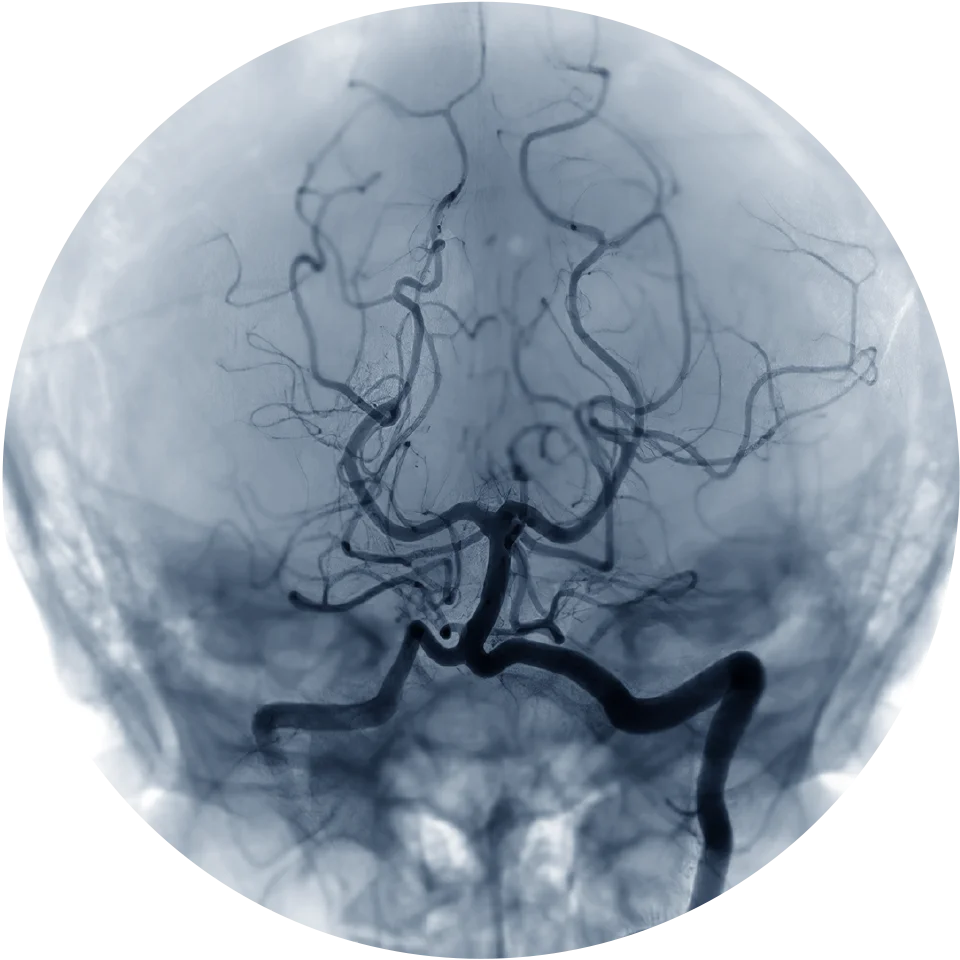

2. Advanced Imaging & Technology

The clinic is equipped with:

- High-resolution ultrasound

- Digital subtraction angiography

- Advanced cath-lab-level imaging

This allows precise diagnosis and accurate treatment planning.